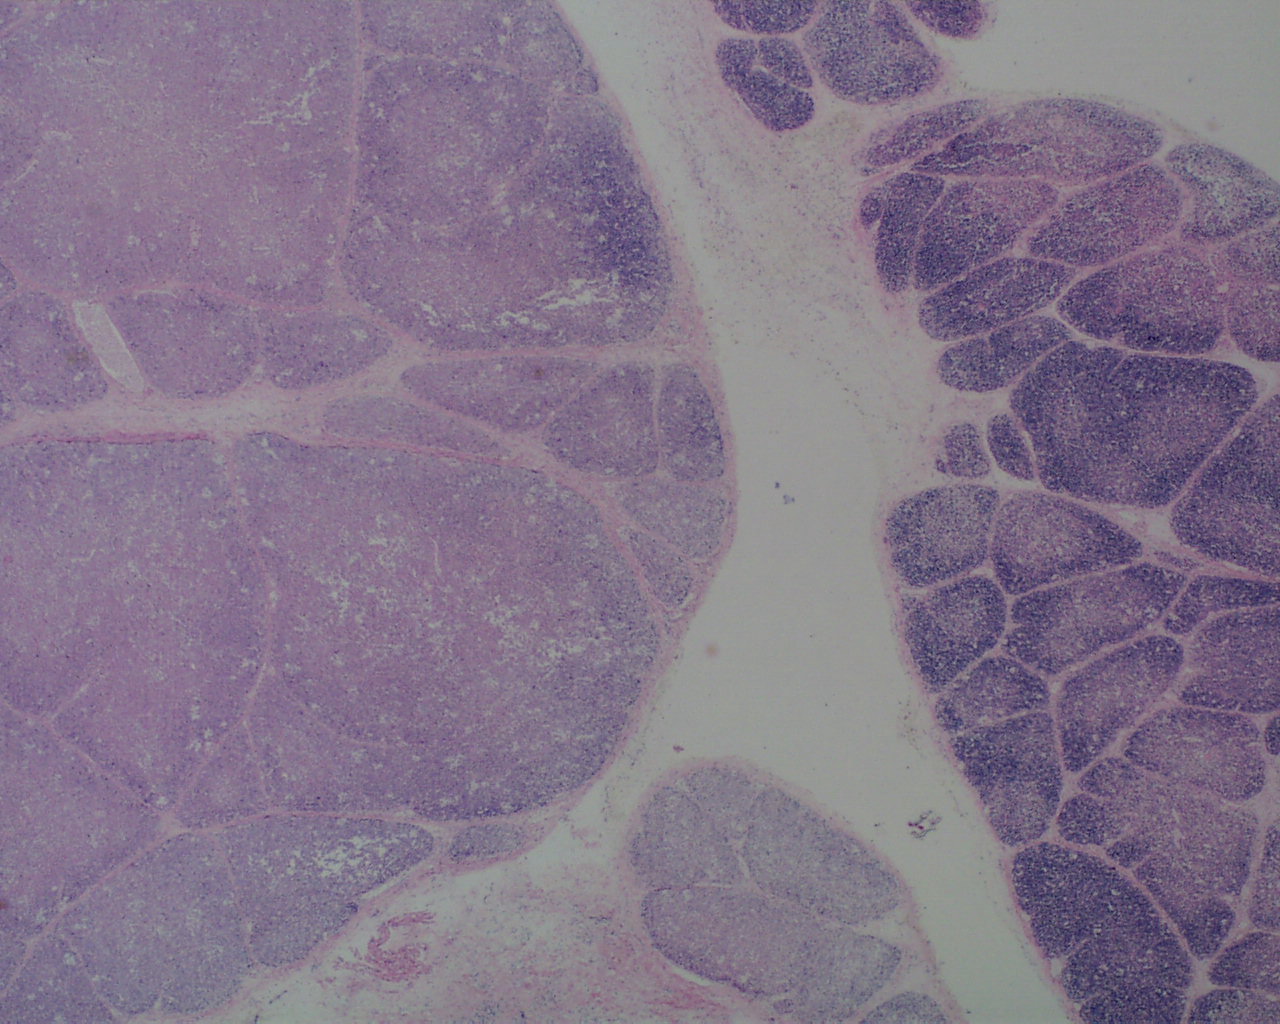

As involution progresses, there will be a progressive loss of cortical lymphocytes. The cortex will appear notably thinned compared to the medulla with thinner lobules and more connective tissue between lobules (Figs 11a, 11b, 12a, 12b, 13a, 13b).

At the extreme, the medulla will appear to have the only small lymphocytes in the thymus, giving an inside out appearance at low magnification (fig 14, 15).

A staging system has been proposed for this progression: stage 0 = no histopathologic changes, stage 2 = starry sky appearance, stage 3 = loss of distinction of the medulla and cortex, and stage 4 = loss of all cortical lymphocytes with an inverted appearance[16]. Based on the clinical histories, the stage has been correlated with duration of involution as follows: stage 0 = 0-12 hours, stage 1 = 12-24 hours, stage 2 24-48 hours, and stage 4 > 72 hours. A continuous stress keeps the thymus involuted, and results in decreased weight as demonstrated in human autopsy and in experimentally in the monkey with repetitive dexamethasone injections [17].The thymic to brain weight usually reflects the histological degree of involution when the small size is due to histological identified involution and not a failure of thymic development.

The complexity of thymic changes is demonstrated in a case of a 22 week gestation infant with a week of preterm premature rupture of membranes who was treated with betamethasone (a synthetic corticosteroid that can cross the placenta to the infant and used to promote lung maturation) and antibiotics. The infant survived for three quarters of an hour. The placenta demonstrated choroamnionitis with some fetal inflammation in the superficial chorionic vessels. The autopsy demonstrated complete involution of the thymus, follicular formation in the spleen, and extensive, intense acute pneumonitis with no growth of microorganisms on lung culture. The thymus demonstrated an inverted picture with no cortex and small lymphocytes in the medulla. The cortical rim demonstrated a compact epithelial layer. (Figs 16, 17) This infant had evidence of acute inflammation, and antibody stimulation, making it impossible to assess the changes due to the exogenous steroid.